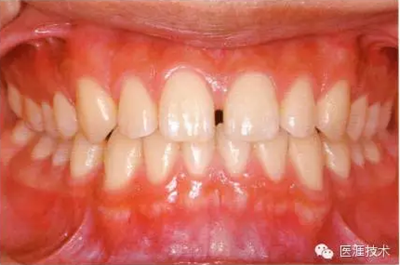

28歲女性的健康口腔內(nèi)部

圖為28歲女性,無特殊全身疾病,不抽煙。10年前來院就診保養(yǎng)3年,期間中斷過,現(xiàn)又開始。齲壞風(fēng)險(xiǎn)高,當(dāng)初初診時(shí)已有好幾顆牙的鄰面有填充物,再填充了3牙的鄰面齲,現(xiàn)牙周組織健康。